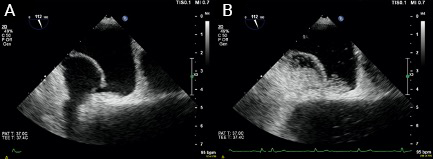

At this point, an intracardiac shunt was suspected and a bubble study with transthoracic echocardiography (TTE) was clearly positive with microbubbles almost completely filling the left heart chambers (figure 1). The dilated aortic root obscured the atrial septum so a PFO or ASD could not be identified. There was no evidence of a pulmonary arteriovenous malformation or hepatopulmonary shunt on CT scan. Transoesophageal echocardiography (TOE) with a bubble study confirmed a PFO measuring 40 mm maximally, causing a right-to-left shunt with large numbers of microbubbles crossing the interatrial septum when the patient was positioned at 45 degrees (semi upright) and less so when he was lying supine (figure 2).